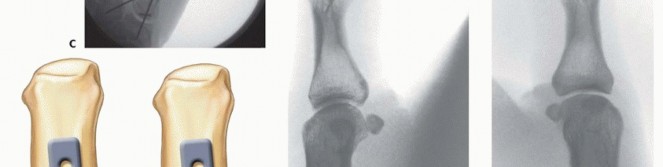

For a large fragment Bennett fracture, the shaft is reduced to the volar-ulnar fragment using a pointed reduction clamp. Provisional fixation is achieved with a K-wire. A 1.5mm or 2.0mm lag screw is then placed perpendicular to the fracture plane. The near cortex must be overdrilled (gliding hole) and the far cortex underdrilled (thread hole) to achieve true interfragmentary compression. The screw head should be countersunk to prevent hardware prominence beneath the thenar muscles.

Fixation Strategies for Rolando and Comminuted Patterns

Rolando fractures present a significantly higher degree of complexity. The classical Y or T pattern often precludes simple lag screw fixation. In these instances, mini-fragment plating is the gold standard. T-plates or specialized condylar plates are contoured to fit the complex geometry of the metacarpal base. The articular fragments are first reduced and provisionally pinned, essentially converting the complex intra-articular fracture into a simpler two-part extra-articular fracture. The plate is then applied to buttress the articular fragments and bridge the metaphyseal comminution to the diaphysis.